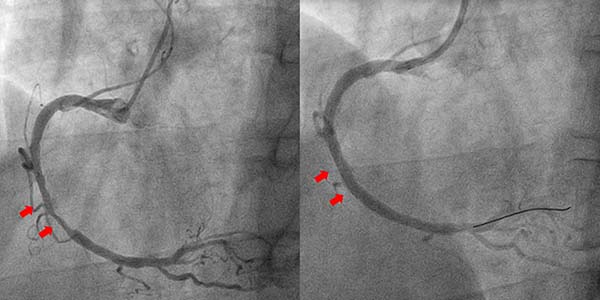

案例1

张先生2025年4月28日因劳累时胸闷就诊于清华大学附属垂杨柳医院心内科,入院后拟择期完善冠脉造影检查评估冠脉。然而术前检查中血常规项目中的轻度贫血及便潜血阳性引起了管床医生的警惕。消化内科会诊认为患者贫血原因需考虑消化道出血导致可能,因患者存在抗血小板类药物使用相对禁忌,遂决定暂停抗血小板类药物使用,为消化内科内镜检查做准备,同时放弃冠脉造影检查并改为完善冠脉CTA检查初步评估冠脉。然而检查结果却不容乐观,冠脉CTA提示张先生冠状动脉多发中-重度狭窄。消化内科与心内科共同评估病情后决定先行胃镜检查,病理结果显示低分化腺癌。需要限期手术,但是合并冠状动脉严重狭窄外科围术期发生急性心血管事件风险极高。而冠心病治疗需使用抗血小板类药物,冠脉介入治疗术中需使用抗凝药,患者消化道出血风险也很高。心内科团队及普外科团队经共同讨论后制定了治疗方案:先由心内科处理冠脉病变,之后由普外科尽早完成切除胃部肿瘤。冠脉造影结果显示:右冠脉严重狭窄。考虑到患者需要尽快接受外科手术,心内科冠脉介入团队讨论后决定应用新型药物涂层支架干预右冠脉(可减少术后双联抗血小板时间至最少1个月)。经1个月双联抗血小板治疗后,经麻醉科、心内科、普外科再次评估后,于2025年6月24日由普外科完成腹腔镜下肿瘤切除术。